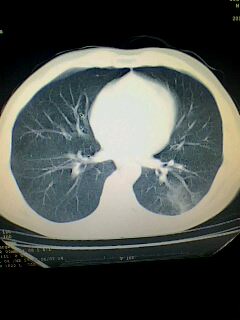

考虑左肺下叶周围型肺癌.图象欠清,请问病人贵更?

考虑左肺下叶周围型肺癌.

图像资料欠清,建议强化,考虑周围型肺癌。

左下肺肿块影,深分叶,考虑肺癌。

左下肺球形病灶,考虑:1:球形肺炎;2:周围型肺癌不除外,建议治疗后复查

不排除左肺下叶周围型肺癌可能!建议穿刺活检!

考虑左肺下叶周围型肺癌并阻塞性肺炎。